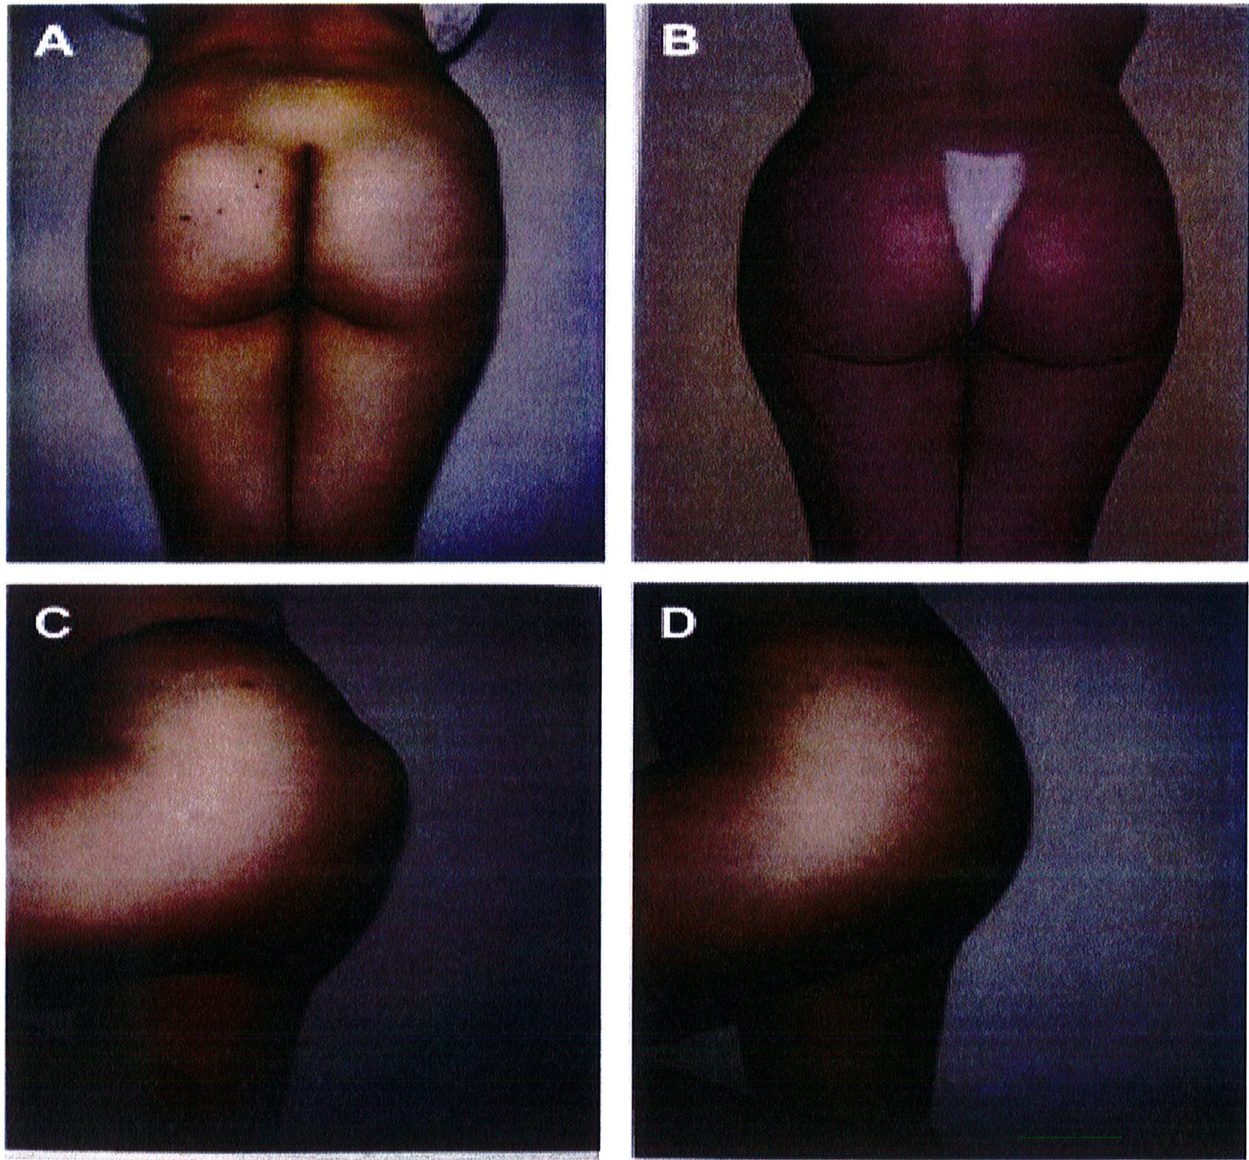

Kết quả phẫu thuật quan sát trên Hình. 3-5.

Hình. 3. (A-H) Tiền phẫu, chu phẫu và sau hậu phẫu 6 tháng của một bệnh nhân nữ 38 tuổi đươc ghép túi đôn mông với thể tích 330 cm3.

Chương 5 : Nâng mông dưới cơ

Hình. 4. (A-I) Hình ảnh tiền phẫu, chu phẫu và sau hậu phẫu 11 tháng của một phụ nữ 25 tuổi đã được thực hiện hút mỡ vùng éo, hông và sau xương vùng, đồng thời ghép khối cấy thể tích 270cm3.

Hình. 5. (A-F) Hình ảnh tiền phẫu và sau hậu phầu 4 tháng của bệnh nhân 67 tuổi, ghép khối implant thể tích 300 cm3.